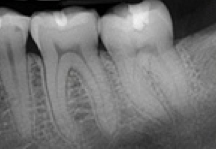

Digital X-rays provide us with more detail viewing and the ability to enlarge a view to look at specific areas in greater depth. In addition, it allows us the capacity to email your x-rays when we collaborate with our local specialists in the area. The biggest benefit is to our patients who receive 80-90% LESS radiation when taking x-rays to examine their teeth, allowing us much more safety on your behalf.